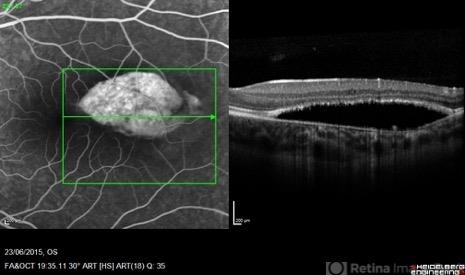

- torpedo maculopathy, optical coherence tomography (OCT), fluorescein angiogram (FA)

- Pierre-Henry Gabrielle, Ophthalmology department, Dijon University Hospital, France

Optical coherence tomography system

Heidelberg Spectralis - Description

- Coupled OCT B-scan and fluorescein angiogram of an asymptomatic 12-year-old girl with torpedo maculopathy of the left eye. One can report complete RPE atrophy at lesion site with window defect on FA and choroidal cavitation on OCT.